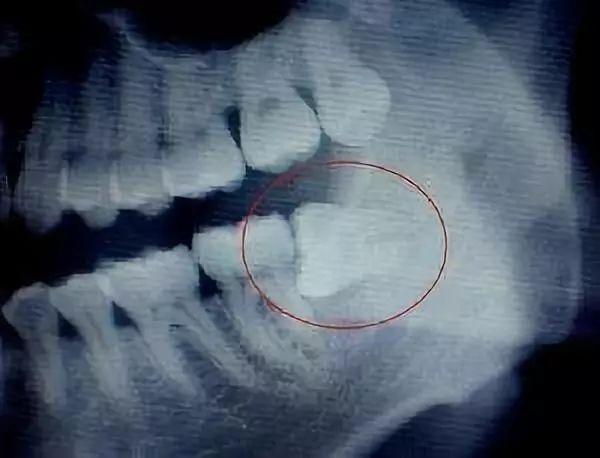

智齒經(jīng)常斜著長,硬的牙冠經(jīng)常頂在鄰牙軟的牙頸部,由于物理擠壓作用,阻生處無法清潔,第二磨牙早于智齒爛牙。

由于智齒經(jīng)常斜著長,硬的牙冠經(jīng)常頂在鄰牙軟的牙頸部,由于物理擠壓作用,阻生處無法清潔,第二磨牙早于智齒爛牙。

一顆橫生的智齒,鉗子是搞不出來的。醫(yī)生可以拿出鍾鑿把它劈開搞出來,也可以拿出渦輪機(jī)把它磨開搞出來,對(duì)患者帶去的影響是一樣的嗎?前者會(huì)造成患者心理恐慌,加重關(guān)節(jié)負(fù)荷,后者會(huì)帶來更高的術(shù)后感染、局部反應(yīng)風(fēng)險(xiǎn),能輕易地判斷說哪個(gè)方法更先進(jìn)嗎?只有適合的,沒有好的,這個(gè)背后體現(xiàn)的是醫(yī)生的經(jīng)驗(yàn)和人文關(guān)懷。